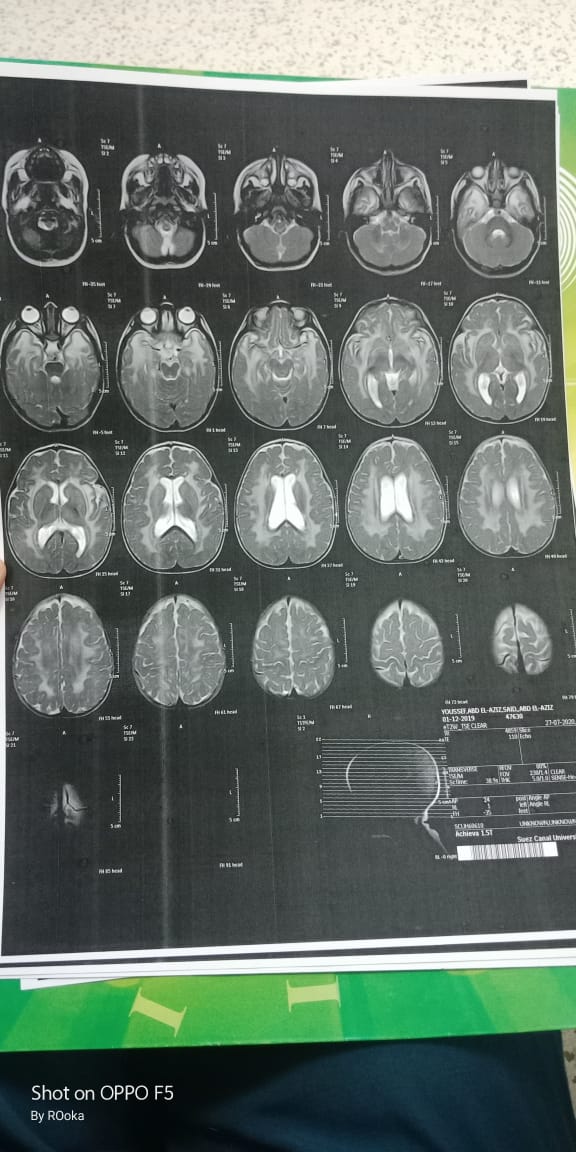

وأضاف عبد العزيز، في تصريحات خاصة لـ القاهرة 24: اكتشفنا مرض يوسف وهو عنده 6 شهور، طلع عنده نقص في المادة البيضاء، ونقص في الأكسجين، مع تآكل في القشرة المخية.

وأكد أن طفله فاقد للحركة والكلام حاليًا، مع تمدد حجم الدماغ، نتيجة معاناته من اختلالات عصبية، التي تنشأ عن المرض، معقبًا: الطفل يحتاج لجهاز طبي يساعد على تخفيف حدة الأعراض، وفقًا لاستشارة الأطباء.